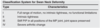

What are the extensor compartments of the wrist and associated pathology?

- EPB + APL = De Quervain’s tenosynovitis

- ECRB + ECRL = intersection syndrome

- EPL = drummer’s wrist, traumatic rupture with DR #

- EDC + extensor indicis = extensor tenosynovitis

- EDM = Vaughn-Jackson syndrome

- ECU = snapping ECU